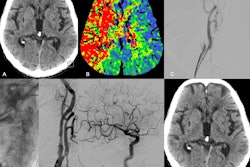

All patients received standard neuroimaging exams – either noncontrast CT, CT/MR angiography, or CT perfusion or MR diffusion-perfusion imaging – at the time of presentation. The researchers analyzed relationships between imaging estimates of irreversibly injured brain tissue and at-risk regions and EVT clinical outcomes.

Based on a standard CT scoring system for stroke severity, EVT improved functional outcomes compared with medical management alone in patients with mild (aGenOR, 1.71), moderate (aGenOR, 2.01), and severe (aGenOR, 1.85) tissue damage, according to the findings.

In addition, across strata for CT perfusion/MRI ischemic core volumes, aGenORs for EVT versus medical management was 1.63 for volumes less than or equal to 70 mL, 1.41 for volumes less than 100 mL, and 1.47 for volumes less than 150 mL.